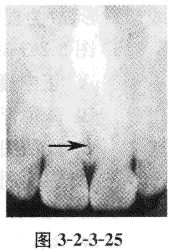

6、图中箭头指示表示的是

【答案】C

【解析】该图箭头所指为位于两中切牙牙根之间,其外围有致密线条。穿过切牙孔中央有一密度低的线条状影像向颌骨后部伸延,将上颌骨分为两半,为腭中缝。